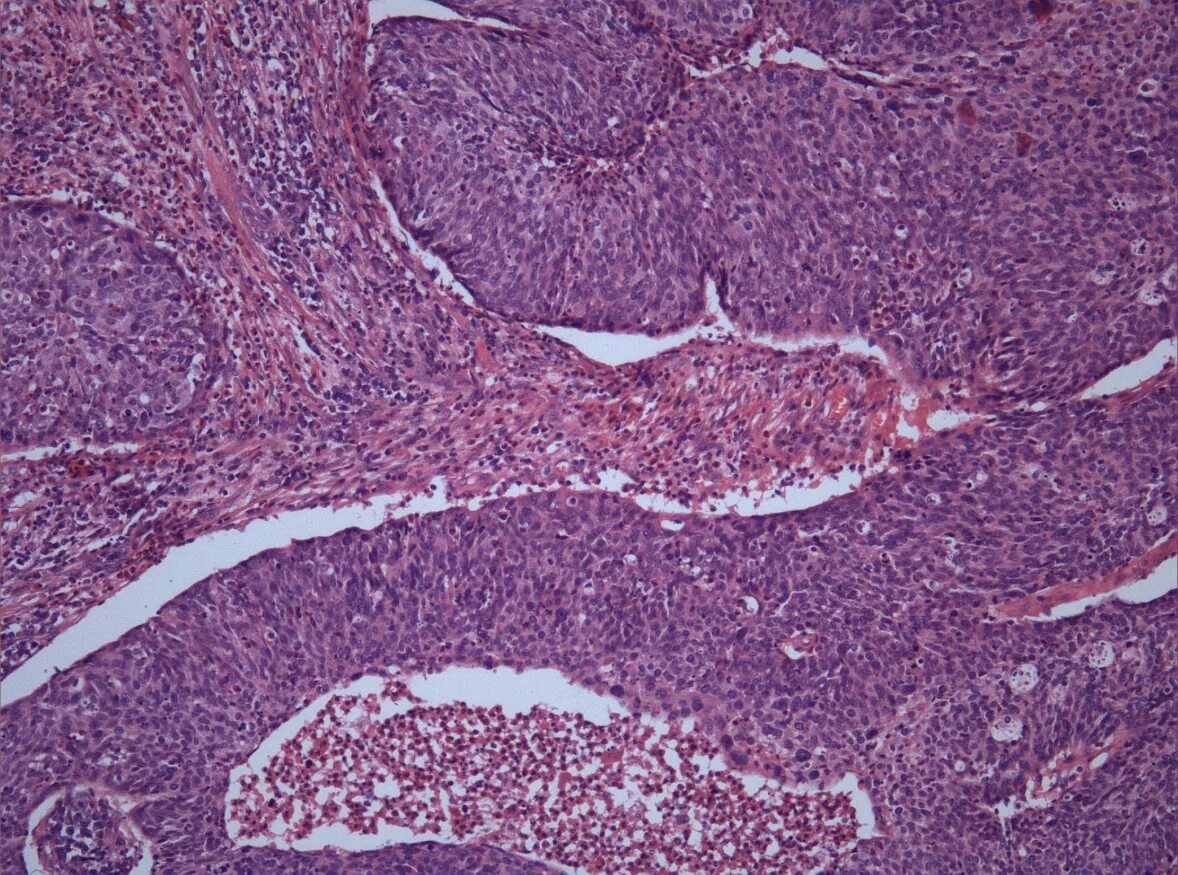

Гистология самара